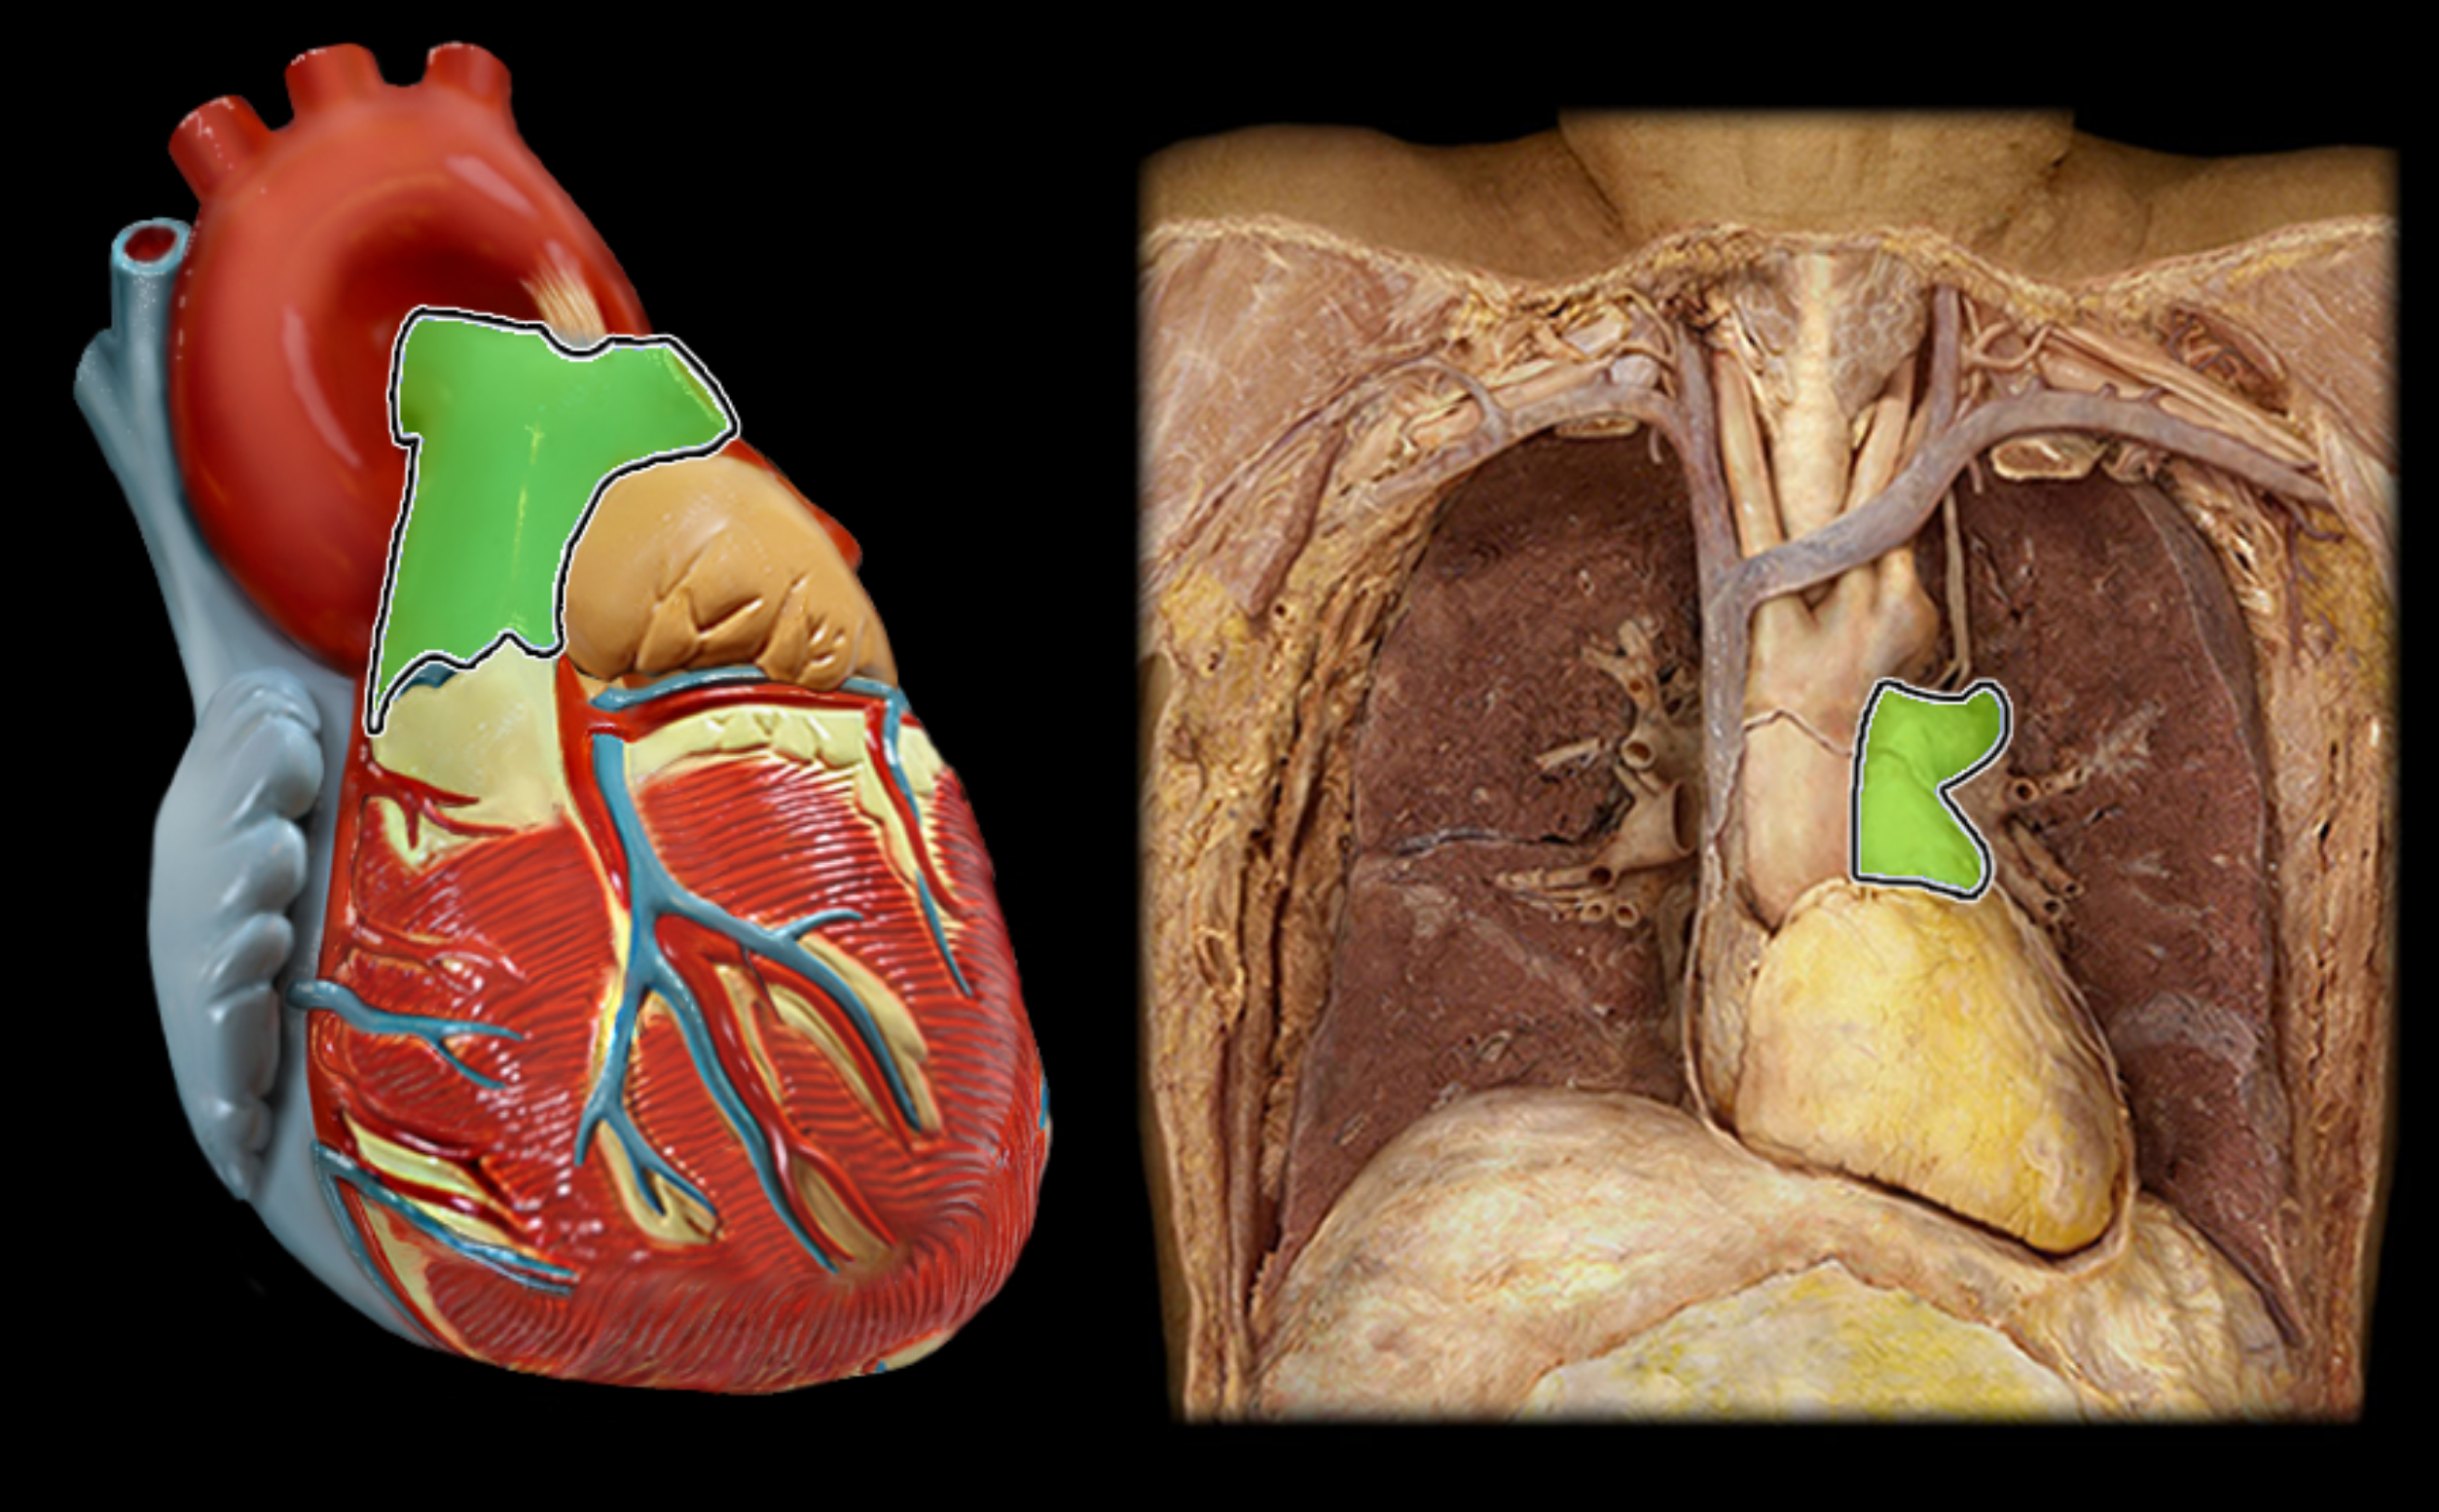

pulmonary trunk

pulmonary artery